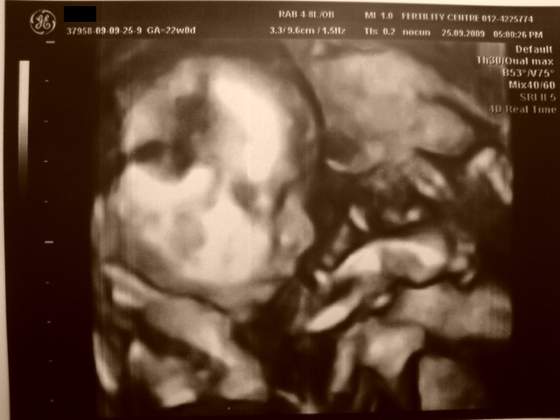

Zatem przedstawiamy naszego synka :-)